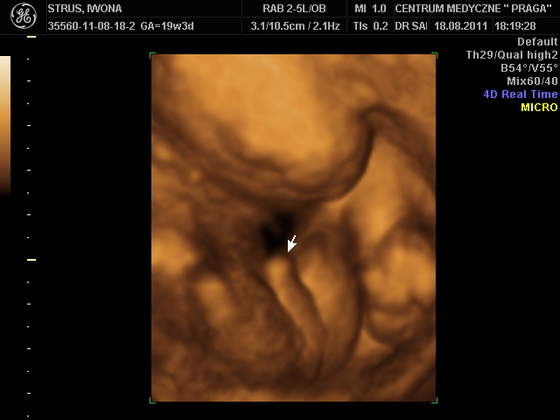

co siusiaka syna Iwaskowego :-o

Ale jaki duuuzi!